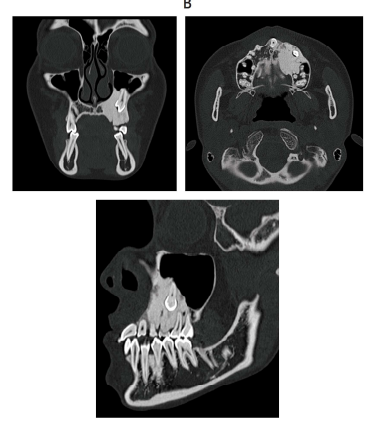

24 歳の女性。乳歯の残存を主訴として来院した。中学生のころから自覚し、矯正歯科治療を希望した際に精査を勧められたという。歯肉に異常所見はない。初診時のエックス線画像(別冊No. 27A)と CT(別冊No. 27B)を別に示す。

疑われるのはどれか。 1 つ選べ。

解答:c

解説:

パノラマ:左側の臼歯部根尖から上顎洞下部にかけてすりガラス状の不透過像

CT:左側上顎洞に埋伏歯と不透過像がみられる。

a 大理石骨病:もっと広がっているはず

b 骨形成線維腫:

c 線維性異形成症:すりガラス状!

d 慢性硬化性骨髄炎:骨髄炎は骨膜反応がみられる。

e セメント質骨性異形成症:多発性のことが多い